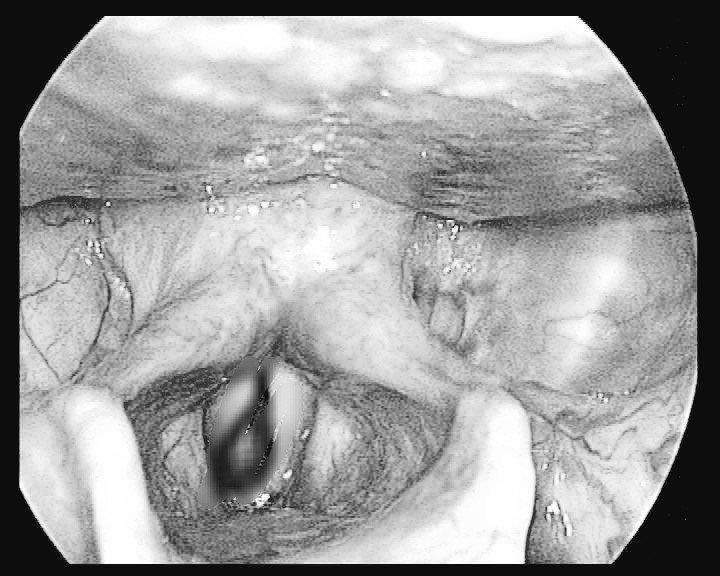

Vào Bệnh viện đa khoa tỉnh Cao Bằng, bệnh nhân được thực hiện các xét nghiệm cận lâm sàng, trong đó có nội soi tai - mũi - họng, các bác sĩ phát hiện trong thanh quản bệnh nhân V. có dị vật là một con đỉa còn sống đang bám vào thanh, khí quản.

Thạc sĩ Bùi Thị Minh Châu, Phụ trách khoa Tai mũi họng, đã phối hợp cùng kíp khoa Gây mê hồi sức tiến hành nội soi gây mê. Trong quá trình nội soi, các bác sĩ gắp ra một con đỉa no máu, dài khoảng 4cm.